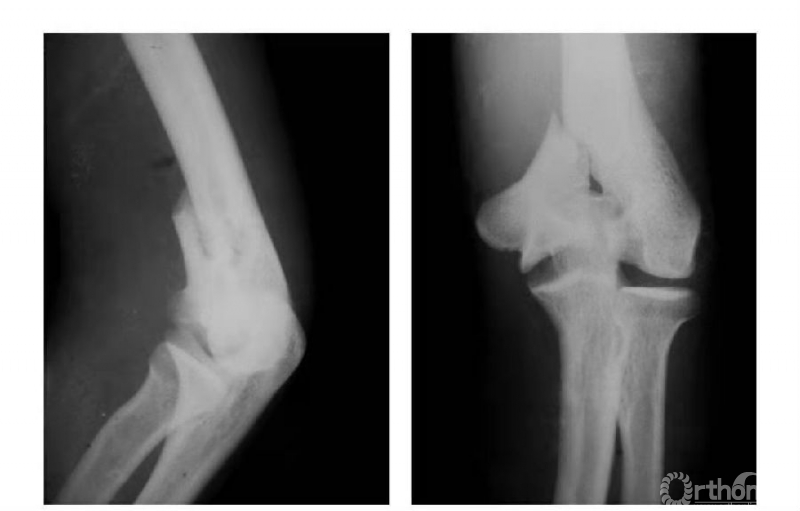

例3:肱骨内髁长斜形劈裂骨折(折线长约10cm)(图3)。

图3

二、陈旧性内髁骨折

例1:肱骨内髁滑车关节面骨折,骨块陷入鹰嘴窝内,致肘内翻畸形(图4)。